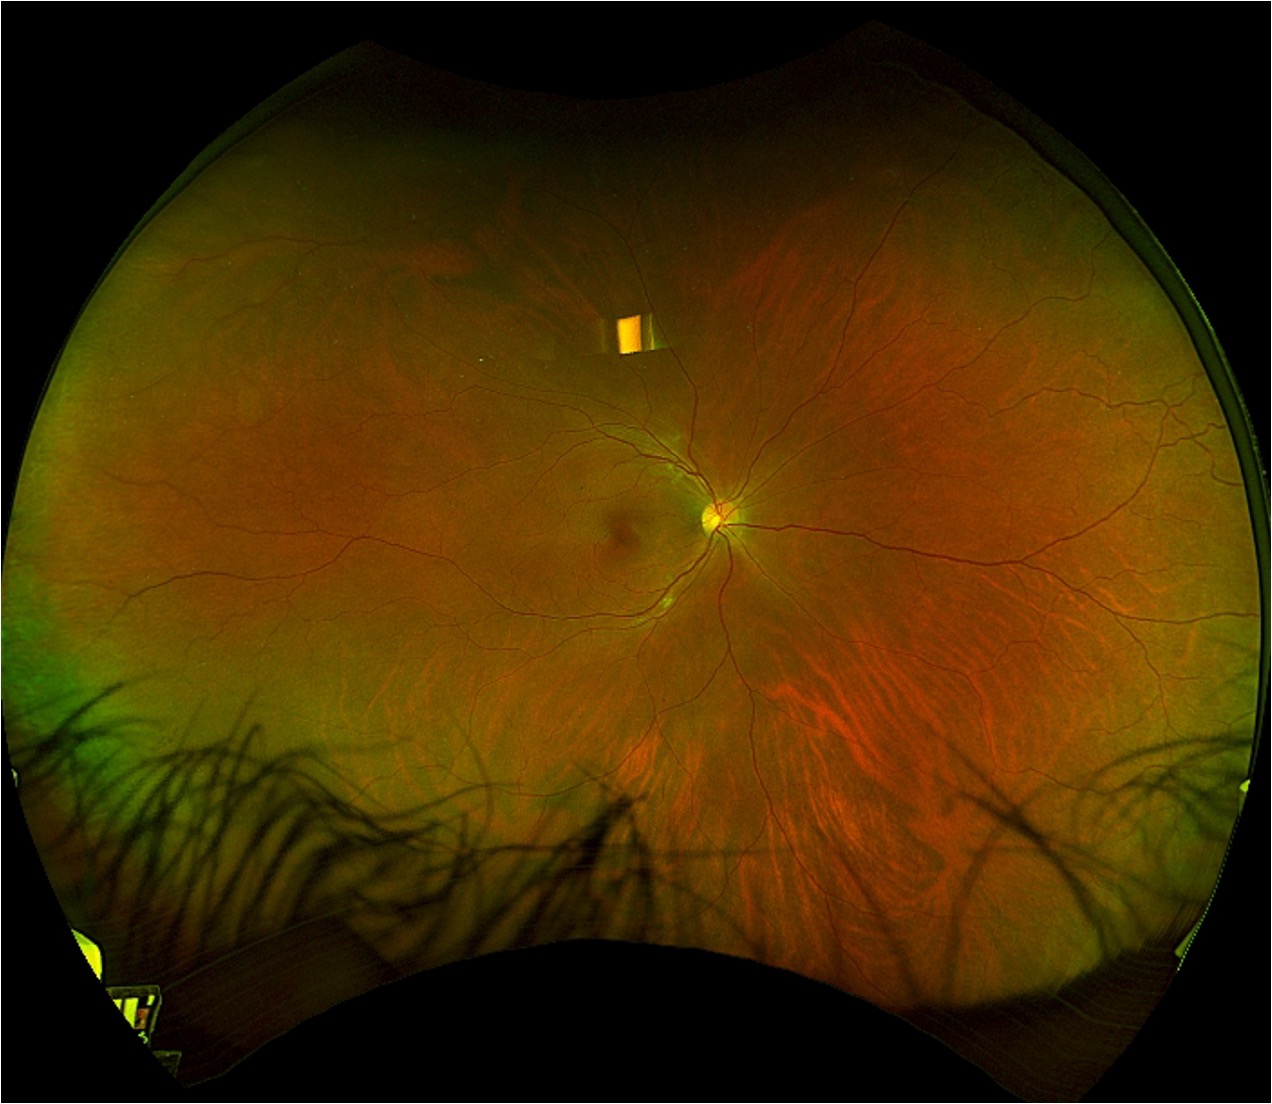

- Fundus photographs demonstrate subtle reddish wedge-shaped parafoveal discoloration in both eyes and cotton wool spots in the left eye.

- Fundus photographs demonstrate a subtle reddish wedge-shaped parafoveal discoloration in the right eye and cotton wool spots in both eyes.